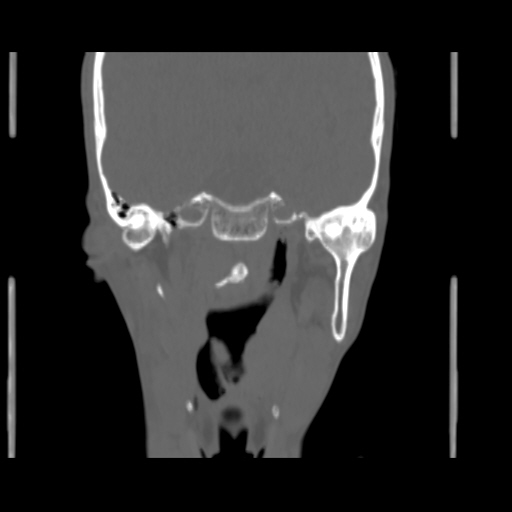

O/E images: